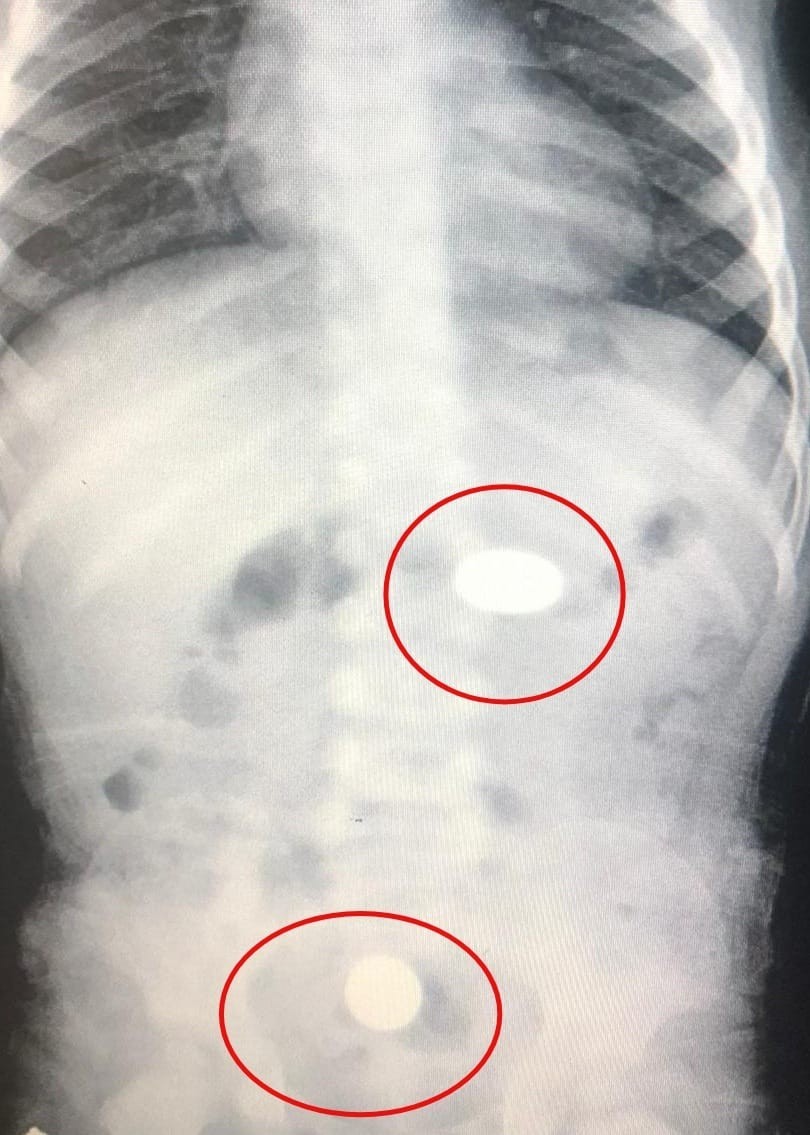

Yapılan tetkiklerde paralardan birinin bebeğin midesinde, diğerinin ise yemek borusunda kaldığı tespit edildi.

Sağlık durumunun iyi olduğu belirtilen Murat Y., tedaviye alındı.